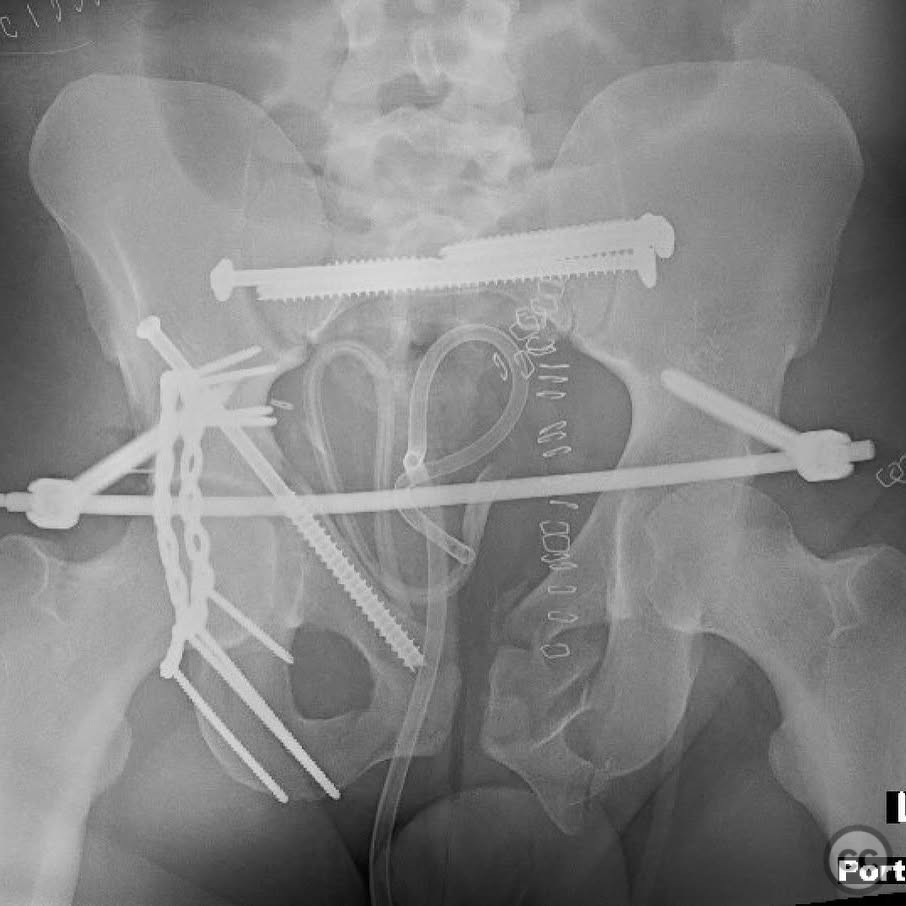

Clinical and radiological findings:  The patient presented with a highly unstable pelvic ring injury and a transverse acetabulum fracture, accompanied by a bladder injury. The bladder injury was addressed emergently with a low vertical midline Pfannenstiel incision for repair, followed by the placement of a low right-sided suprapubic catheter. Radiological imaging confirmed the transverse acetabular fracture and disruption of the left sacroiliac joint, along with a displaced sacral fracture.

Patient positioning:  The patient was positioned supine for the initial stage of pelvic ring stabilization.

Anatomical surgical approach:  For the pelvic ring stabilization, a posterior approach was employed to access the left sacroiliac joint and sacral fracture. In the second stage, a Kocher-Langenbeck approach was planned for acetabular ORIF, with potential anterior column access through a modified Stoppa approach.

Operative remarks:

The surgical team emphasized the importance of achieving an anatomical reduction of the acetabulum while ensuring stable fixation of the pelvic ring. The presence of the suprapubic catheter necessitated careful planning to avoid interference with surgical access and fixation. The decision to prioritize pelvic ring stabilization first was based on providing a stable segment for accurate acetabular reconstruction. Intraoperative challenges included ensuring precise screw trajectory for sacral fracture fixation and managing potential displacement during reduction maneuvers.

Orthopaedic implants used:   Lag screws for sacroiliac joint and sacral fracture fixation, external fixator for posterior ring stabilization, potential plate and screw constructs for acetabular ORIF through Kocher-Langenbeck and modified Stoppa approaches.